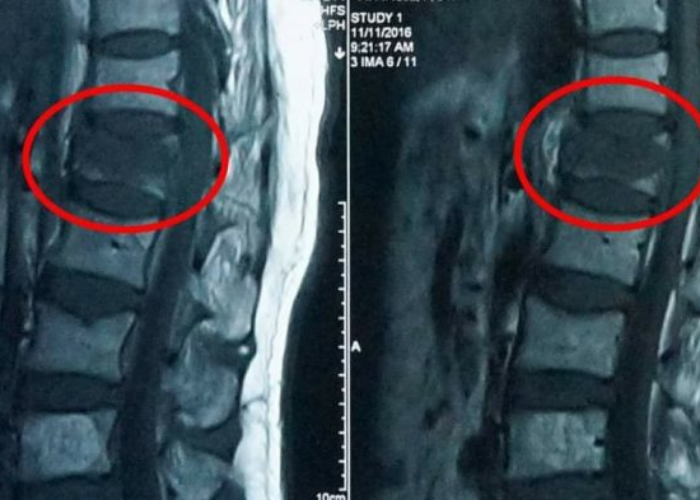

Hình ảnh MRI của bệnh nhân xẹp đốt sống.

MRI cột sống

MRI là phương tiện rất quan trọng trong chẩn đoán:

• Phân biệt xẹp đốt sống mới hay xẹp cũ

• Đánh giá tình trạng phù tủy xương

• Loại trừ các nguyên nhân nguy hiểm khác như:

• U cột sống

• Nhiễm trùng cột sống

• Di căn xương

MRI đặc biệt cần thiết khi người bệnh đau nhiều nhưng hình ảnh X-quang chưa rõ ràng.